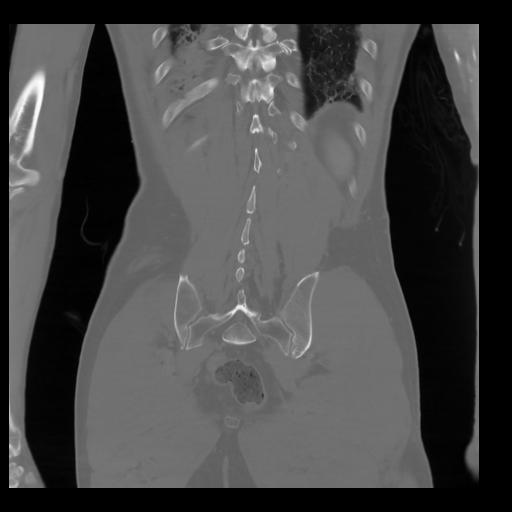

35 CUERPO,CE,Coronal,3.000,CUERPO,Coronal,